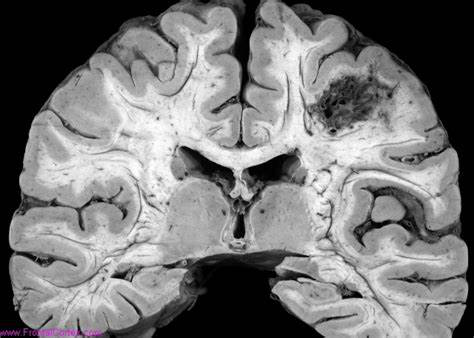

脑动静脉畸形(BAVM)是指一组异常的脑血管,包括供血动脉、引流静脉和中间的异常血管集合,称为nidus。淋巴结的血管通常被称为毛细血管,但组织学检查显示一个模糊不清的壁结构,较好描述为动脉化静脉。它们的功能当然不是毛细血管,因为它们不参与滋养周围的大脑,只是把动脉血分流到收集静脉。

BAVMs较常在脑实质内出血后被诊断出来。大约1%的中风患者和15%的自发性颅内出血患者的病因是BAVM引起的出血。每年再出血的风险估计为每年2-4%,但这些估计值来自于带有程度选择偏差的研究。BAVMs无疑是动态病变,并经历自发演变。诊断时间可能代表病变或周围大脑无法再进行补偿的一段时间,因此外观可能随之改变。对患者的长期血管造影随访显示了这种演变,病变大小增大或减小,甚至完全消退。

对于AVMs,不管出血没出血,都要采取治疗。那么,脑动静脉畸形应该选择什么手术好呢?对于脑动静脉畸形目前常用的手术便是显微外科手术了。开颅显微外科切除术是一种常见的AVMs治疗方法,其主要目的是完全治愈:顺利和完全切除AVMs以消除与其潜在破裂相关的残疾和死亡风险。这种治疗方法的步骤包括:(1)开颅获得AVMs的充分暴露,包括其供血动脉和引流静脉;(2)分离并孤立供血动脉:(3)围绕畸形血管团分离相邻脑实质和周围神经血管结构;(4)切断引流静脉;(5)关闭切口。